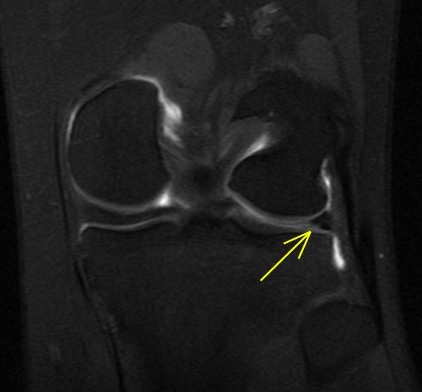

Figure 2 for case Lateral meniscus flap tear and adjacent stress fracture

Figure 2

Knee arthrogram showing lateral meniscus flap tear and adjacent stress fracture.

Lateral meniscus flap tear and adjacent stress fracture